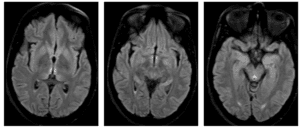

Her Eeys Had the Clue!

All you need is to look at her eyes!